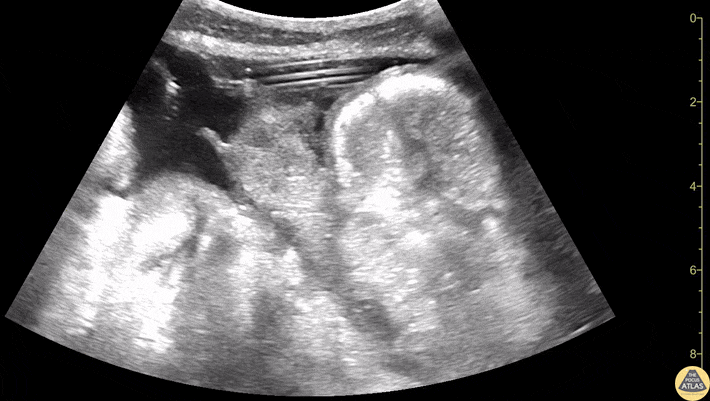

Drainage tube within a located liver fluid collection. Contributors: Dimitri Livshits, DO; Jane Belyavskaya, MD; Chris Hanuscin, MD Kings County/SUNY Downstate